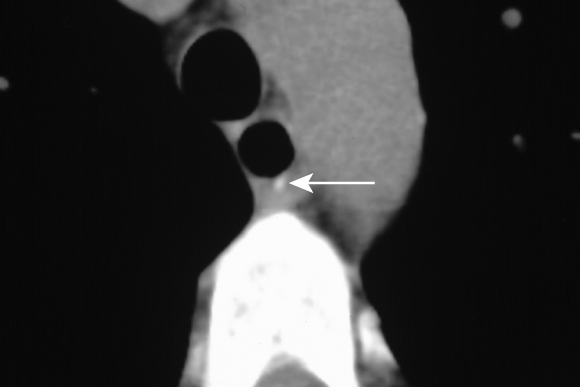

The patient was admitted and managed with nil by mouth, intravenous fluids, triple intravenous antibiotic therapy (ampicillin 1 g four times a day, gentamicin 5 mg/kg daily [with subsequent doses titrated according to drug level], metronidazole 500 mg twice a day), intravenous omeprazole 40 mg three times a day, and frequent observation. Her fever resolved within 24 hours, but her C-reactive protein level rose to 18.2 mg/L (reference range, 0–8.0 mg/L). A second CT scan, with water-soluble contrast, showed intramural contrast with no extravasation, consistent with a partial perforation of the oesophagus (Box 1). Gastroscopy revealed a 10 cm longitudinal mucosal/submucosal tear in the left posterolateral wall of the oesophagus 3 cm above the gastro-oesophageal junction (Box 2A), and a small sliding hiatus hernia. The rest of the oesophagus, stomach and duodenum were normal.